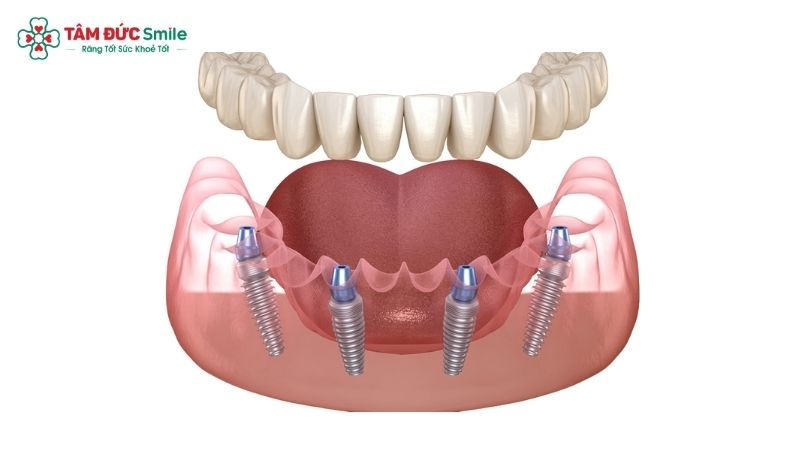

All-on-4 implant treatment is a modern approach to full arch restoration that uses four dental implants to support a fixed, implant-supported prosthetic bridge. Instead of placing individual implants for every missing tooth, this technique strategically positions two implants vertically in the front of the jaw and two implants at an angle in the back. This angulation maximizes contact with available bone and enhances primary stability.

During surgery, four implants are placed into the jawbone. The two anterior implants are positioned vertically, while the posterior implants are tilted at an angle. This approach improves stability and avoids critical anatomical areas such as the maxillary sinus or inferior alveolar nerve.

One defining feature of All-on-4 implant therapy is immediate loading implants. In many cases, a temporary fixed prosthesis is attached within 24 hours after surgery.

This means patients do not have to remain toothless during healing. They leave the clinic with a functional set of teeth that allows them to speak, smile, and eat soft foods almost immediately.